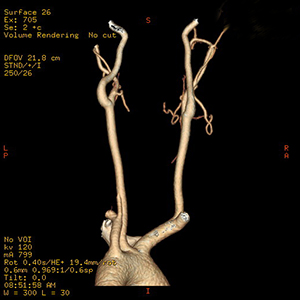

Computed tomography angiography (CTA) is an imaging test. It uses X-rays and computer technology to make detailed pictures of your arteries (blood vessels). Before the test, an X-ray dye (contrast medium) is injected into your vein. The dye makes it easier to see your blood vessels on the X-ray. Pictures are then taken with the CT scanner. A computer turns the images into 2-D and 3-D pictures.

| CTA can make 3D images, such as the carotid arteries shown here. |